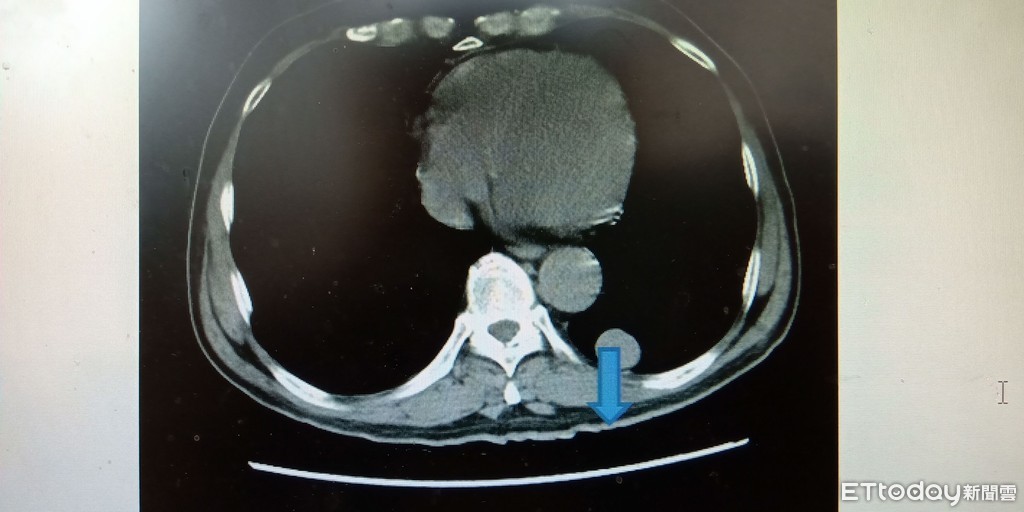

▲一名70歲王老翁,久咳不癒後至安南醫院就診,理學診斷發現罹患罕見「肺內異位性甲狀腺」。(圖/記者林悅翻攝)

安南醫院呼吸照護中心主任劉建興醫師說此一罕見的病例職業為魚池看僱工,沒有甲狀腺病史,是因為病人抽煙50年後所引起發的慢性咳嗽氣喘,也就是一般通稱的慢性阻塞性肺疾病,來到醫院求診拍了胸部X光片,發現在左下肺有一個錢幣型陰影,大概是2.8公分的直徑大小,緊貼近左下肺葉後的胸部,病人除了呼吸道的症狀例如咳嗽、氣喘、胸悶、胸痛以外,並沒有甲狀腺亢進或低下的症狀如心悸、手部顫動、體重減輕,還有眼睛突出等症狀,而檢驗病人甲狀腺荷爾蒙結果也都在正常範圍裡面。

劉建興醫師指出,病人情況可以使用支氣管鏡切片診斷,也可以使用電腦斷層導引切片檢查,不需要外科開胸診斷,就可以來取出這個錢幣型陰影的組織做病理切片檢查,病理切片組織檢查結果為「肺內異位性甲狀腺」。這種肺內異位性甲狀腺的文獻報告大部分都是單一個異位性甲狀腺,只有兩個案例是兩側肺裡面有異位性甲狀腺。